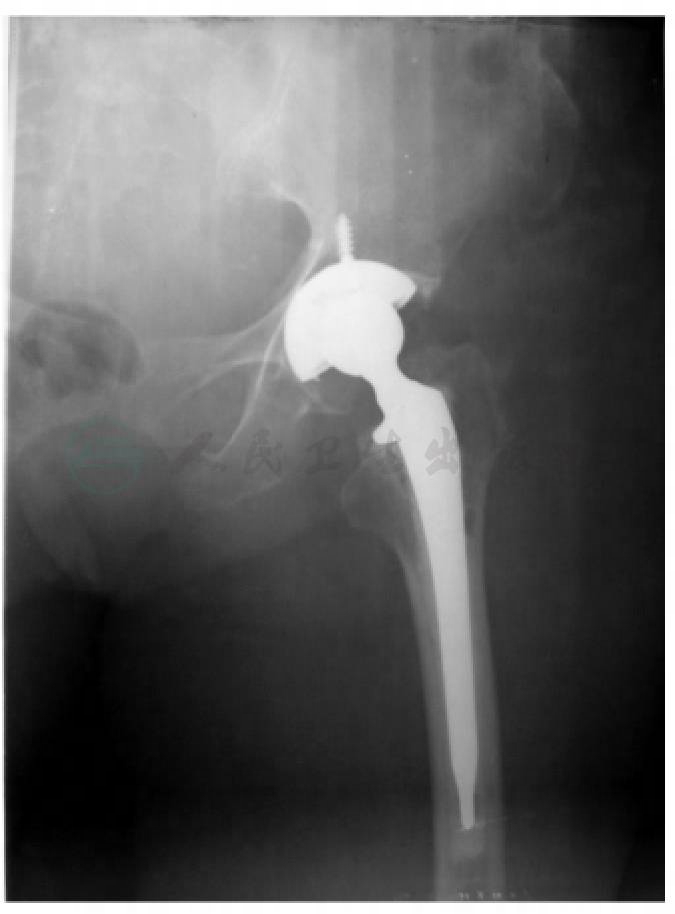

术后嘱患者卧床,患肢给予T形矫正鞋佩戴固定于中立位。术中放置引流管1根,术后需严密监测引流量变化及患者血红蛋白及红细胞计数,术后48小时引流量明显减少,且24小时内小于30ml则拔除引流管。术后行X线检查示人工髋关节假体位置良好(图5)。术后第3天即嘱患者坐起并加强翻身(两腿之间夹枕),开始患肢的等长肌肉力量练习,并开始患者被动活动训练(CPM)。患者术后12小时即开始低分子肝素皮下注射抗凝治疗,使用预防剂量4000U,每日一次,直至拆线出院。患者术后1周,开始扶拐或助行器部分负重站立练习。定期行X线片检查观察假体情况,加强护理,术后3月内避免负重、深蹲及髋关节过度内收活动。该患者术后3个月复查,疼痛明显缓解,假体位置良好。

图5 术后髋关节正位X线片